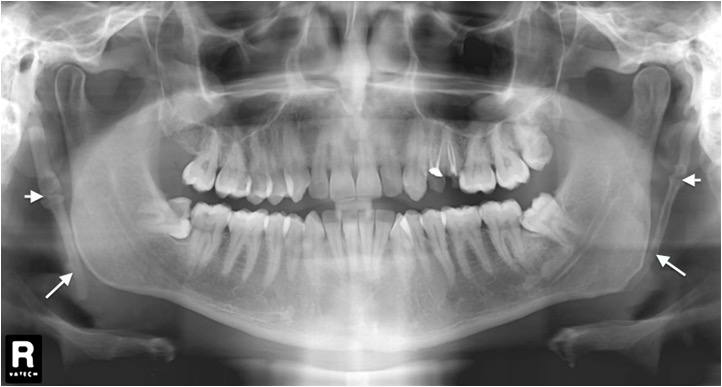

4. What condition can be seen in the following X ray?